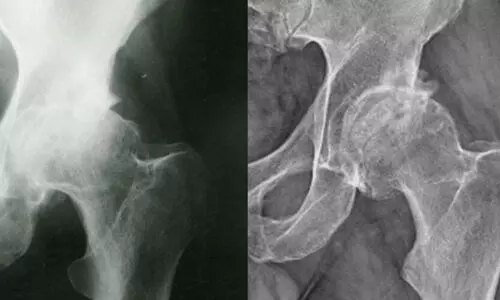

അവാസ്‌കുലര്‍ നെക്രോസിസ് അഥവാ എവിഎന്‍ എന്ന പേരില്‍ അറിയപ്പെടുന്ന ഈ എല്ലു രോഗം അമിതമായി സ്റ്റിറോയ്ഡ് കലര്‍ന്ന മരുന്നുകള്‍ ഉപയോഗിച്ച് കൊവിഡ് രോഗത്തിന് ചികില്‍സ തേടിയവരിലാണ് കണ്ടുവരുന്നത്. ഈ രോഗം ബാധിച്ചവരില്‍ രക്തചംക്രമണം കുറയുന്നതിന്റെ ഭാഗമായി എല്ലിന്റെ കോശങ്ങള്‍ നശിച്ചുപോകുന്നു. എല്ലില്‍ പൊട്ടലുകള്‍ക്ക് ഇത് കാരണമാവും. സന്ധികളില്‍ എല്ലുകള്‍ സ്ഥാനം തെറ്റാനും പൊട്ടാനും തുടങ്ങും.